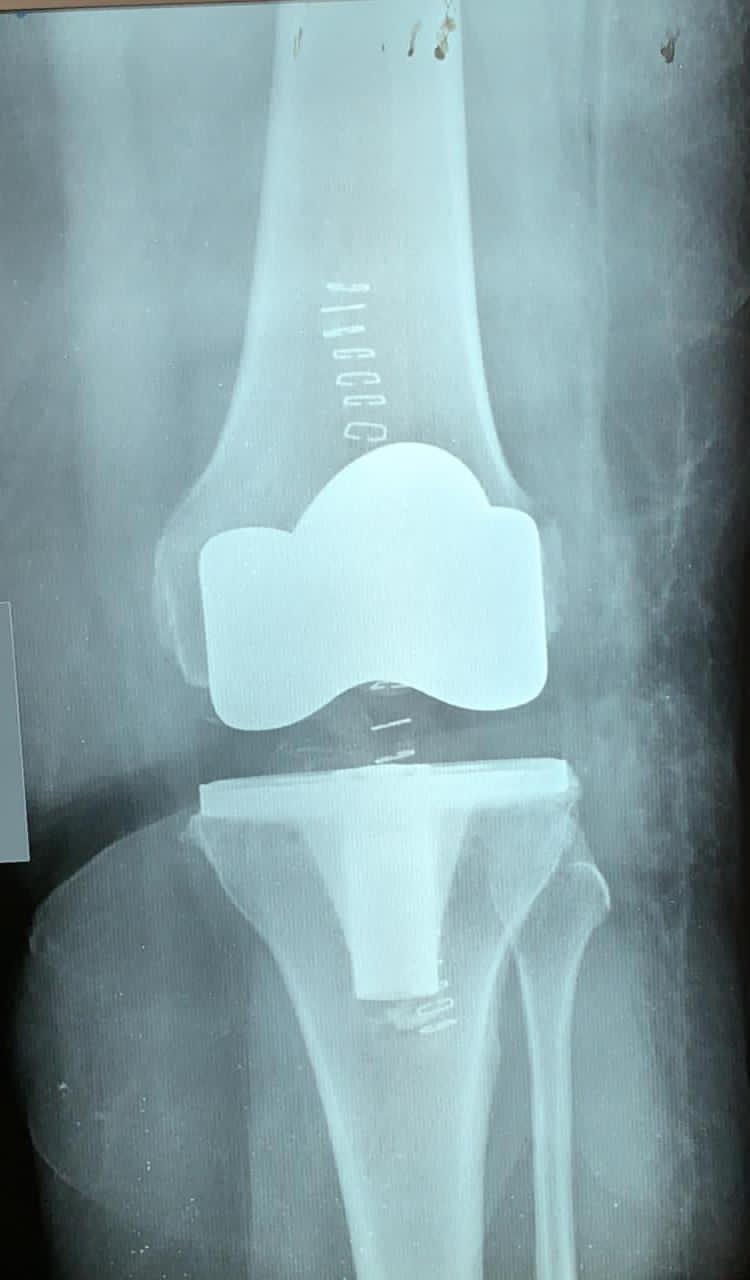

وأكد الطبيب “الشايجي”، أنه وبتوفيق من الله- تمكن الفريق الطبي من إجراء العملية بنجاح وهي استئصال مفصل ركبة واستبداله بمفصل صناعي؛ وقد بدأت المريضة برنامجها بالحركة والمشي؛ لتكون ثاني حالة من حالات تغيير مفاصل الركبة في مستشفى وادي الدواسر العام، بدعم من مدير عام الشؤون الصحية بمنطقة الرياض الدكتور حسن بن علي الشهراني ، ومتابعة المساعد للخدمات العلاجية الدكتور علي بن سليمان الجمعة ، وكذلك إدارة المراكز المتخصصة والطبيب الزائر بصحة الرياض.